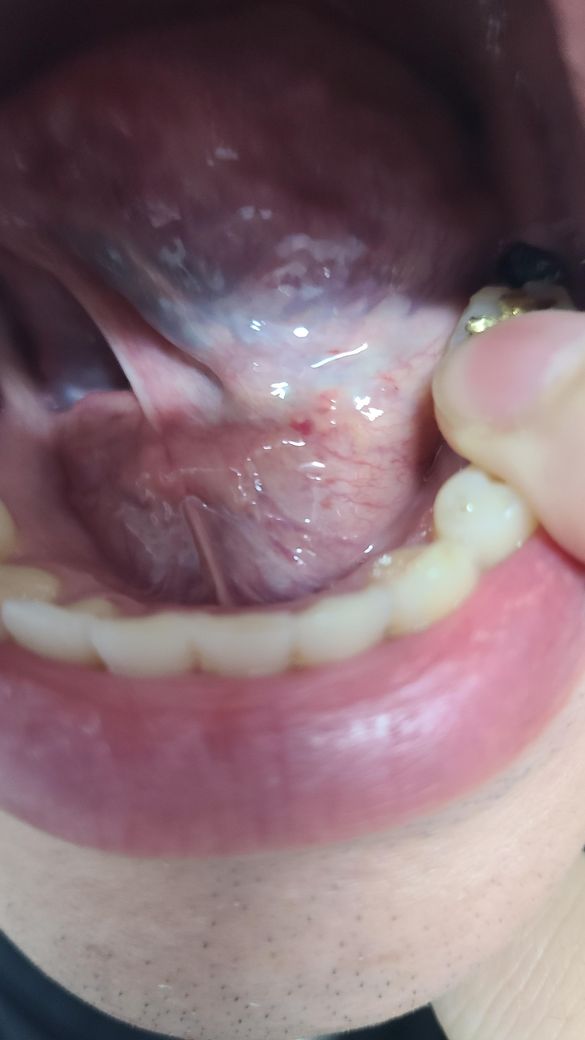

혓바닥 밑에 빨간 점이 있는데 이게 왜그런거져?

양치하다가 혓바닥 밑에 빨같에 점들이 보여 질문드려요 지금 충농증 밑 임파선욤으로 치료를 받고 있습니다 다른 이상이 있는게 아닌지 궁굼 합니다

• 1번 째 사진

일반적으로는 구강 내 염증이나 자극으로 인한 증상일 수 있습니다. 충농증(부비동염)과 임파선염으로 치료 중이라면, 면역 체계가 약해져서 구강 내 염증이나 감염에 더 민감할 수 있습니다. 혀 밑의 빨간 점들이 계속 지속되거나 통증, 부종 등과 함께 나타나면, 다른 감염이나 구강 질환일 수 있으므로, 병원에서 진료를 받아보는 것이 좋습니다